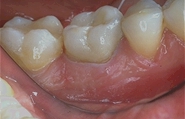

• Couronne céramo-métallique

C’est la couronne la plus utilisée . Il s’agit d’une armature en métal recouverte de céramique (porcelaine dentaire).

Ceram4.jpeg (8251 octets) Ceram6.jpeg (13851 octets) Ceram7.jpeg (12411 octets)

Les dents sont préparées avec les deux techniques de reconstitution décrites plus haut. Les armatures sont recouvertes de céramique.

Rendu esthétique final optimum.